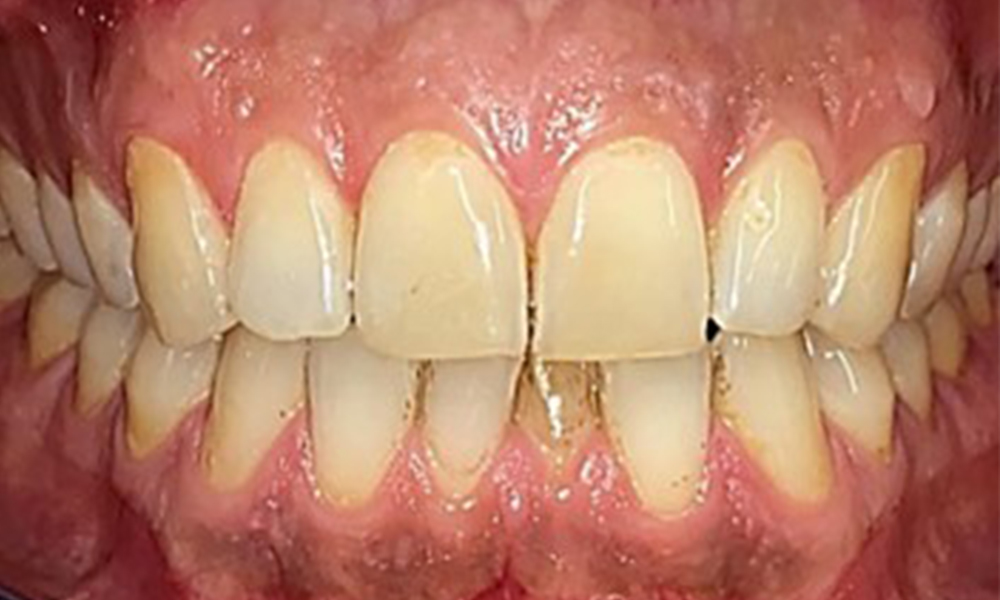

Dentaler Befund

Dental zeigt sich ein vollbezahntes Gebiss mit 28 Zähnen. Auffällig sind Erosionen und Attritionen

(Abb. 4, Abb. 5). Der Patient trägt seit vielen Jahren nachts eine Schiene mit adjustiertem Aufbiss aufgrund Bruxismus. Die Erosionen sind auf den langjährigen Konsum isotonischer Getränke zurückzuführen. Parodontaler Knochenverlust und aktive kariöse Läsionen sind nicht vorhanden.